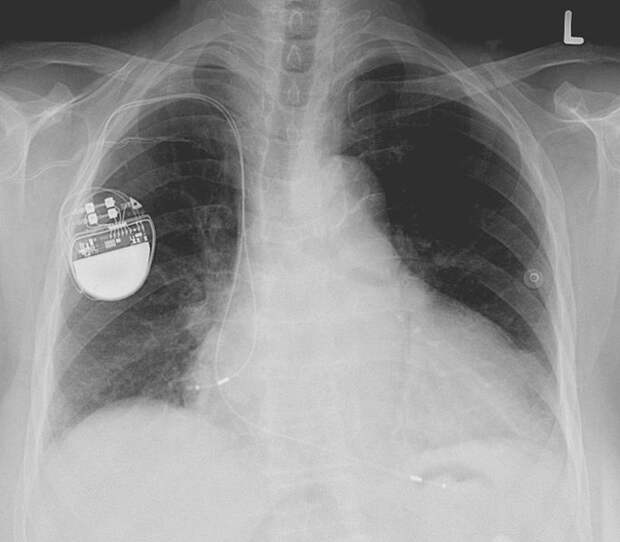

1. Pacemakers

Pacemakers have been around for a while, but they used to be pretty clunky until a gentleman named Wilson Greatbatch, picked up the wrong resistor one day while working on an audio recording device. This resulted in the device giving off a rhythmic pulse which he realized could be used as an implantable pacemaker!